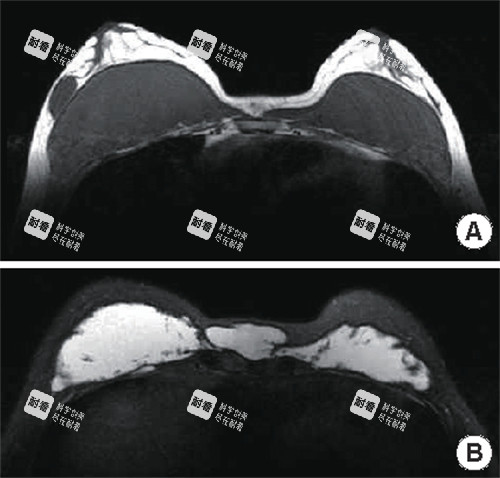

高分辨率超声联合MRI进行术前评估,进一步支持了手术方案的个体化与科学性。